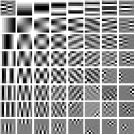

We pre-learn MARS models with different numbers of layers (depths) with transforms. The models are learned from overlapping patches extracted from five XCAT phantom slices. The number of pixels and the number of overall training patches are about and , respectively. The training slices are displayed in the supplement (Fig. 13). The patch stride is . We choose , , , , and layers, respectively, during training, which corresponds to ST, MARS2, MARS3, MARS5, and MARS7 models. We initialize the MARS learning algorithm with the 2D DCT matrix for the transform in the first layer and identity matrices for transforms in deeper layers. For each model, we ran 1000 to 1500 iterations of the block coordinate descent training algorithm to ensure convergence. We choose for ST, , , for MARS2, , , , , for MARS3, , , , , , , , , for MARS5, , , , , , , , , , , , , for MARS7. Fig. 3 shows some of the learned transforms, with each transform matrix row displayed as a square patch for simplicity. The first layer transform in the models typically displays edge-like and gradient filters that sparsify the image. However, with more layers, finer level features are learned to sparsify transform-domain residuals in deeper layers. Nonetheless, the transforms in quite deep layers could potentially be more easily contaminated with noise in the training data, since the main image features are successively filtered out over layers.